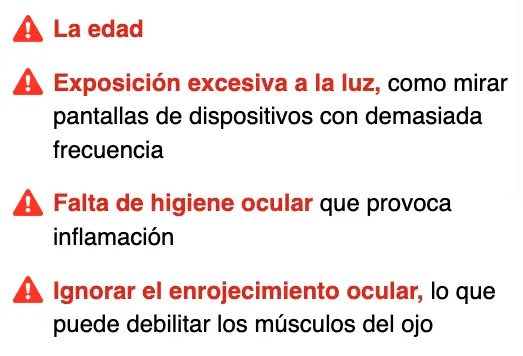

¡Esta es la causa!

Los ojos son una de las partes más importantes del cuerpo. Además de ser el órgano de la visión, también actúan como guardianes, percibiendo todo aquello que nos genera incomodidad. Cuidar la retina es una de las claves para mantener una buena salud ocular. La retina desempeña un papel vital, ya que se encarga de procesar la información visual que luego se transmite al cerebro. Sin embargo, existen varios factores que pueden deteriorar la visión: